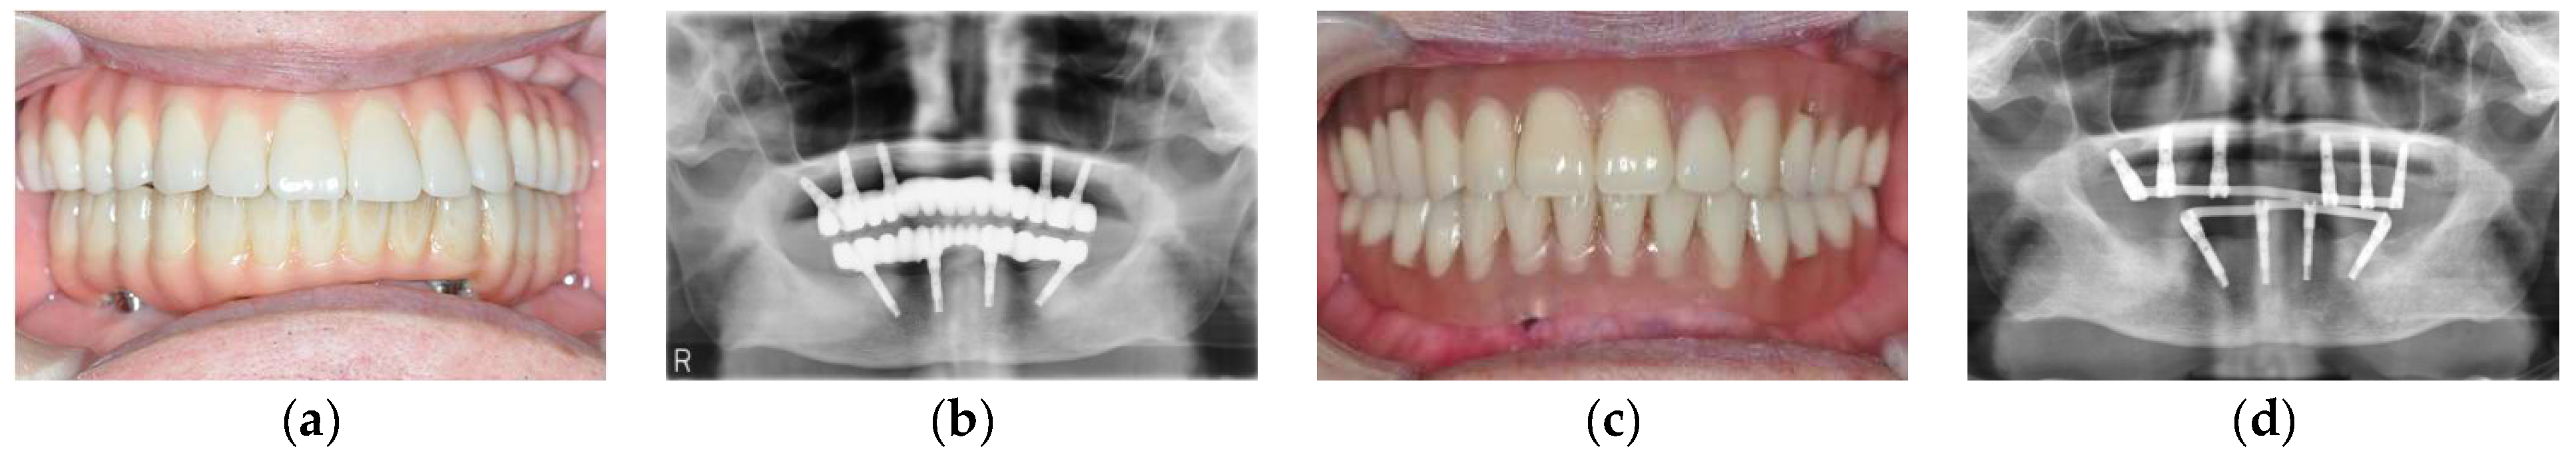

3.3. Conversion of the Suprastructure from a Fixed to Removable Prosthesis without Implant Loss